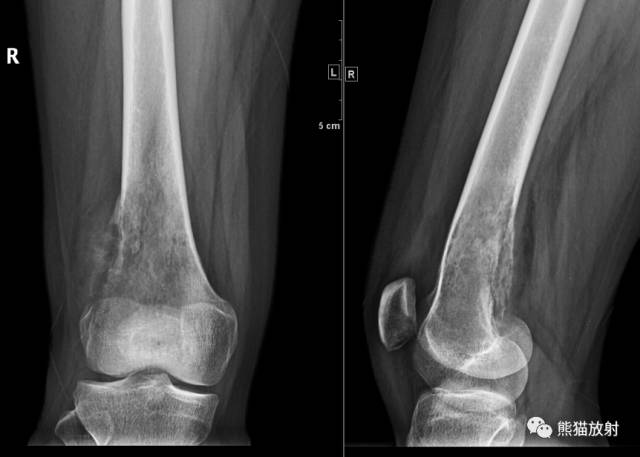

↓ 胫骨上端骨巨细胞瘤

↓ 胫骨上段纤维结构不良(女12岁)